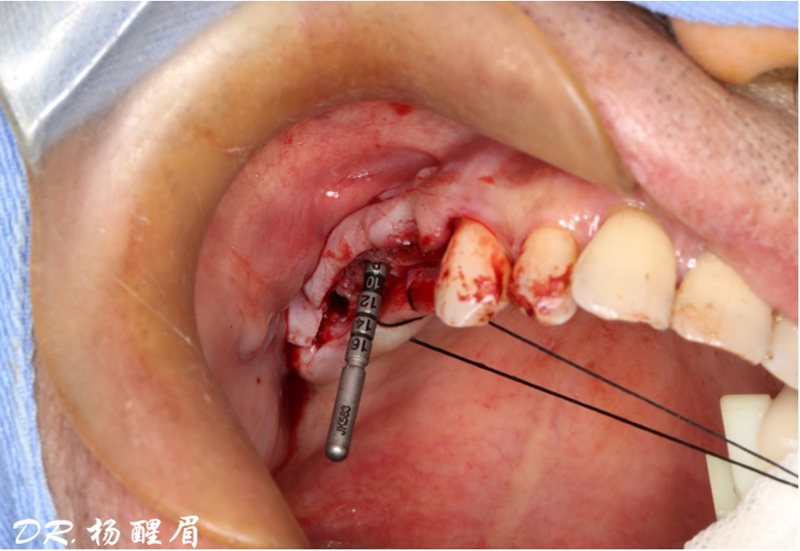

®對植體深度及方向進行確認

®完成3顆植體的植入,植體位點如術前方案設計,均在同軸線。

®進行縫合

®多顆植體位點及角度的精確性,確保后期修復方案順利完成,也使患者能在使用過程中承受最佳的咬合力

®該患者需連續(xù)種植三顆植體,手術難度高。需保證相鄰植體位置關系符合種植要求。徒手種植難以保證其位置一致性。

®主刀醫(yī)生經(jīng)驗豐富,通過石膏模型排牙確定咬合關系,放射阻射材料提前放入缺牙區(qū),確定CBCT中牙冠位置,擺放種植體。遵循修復引導種植原則。